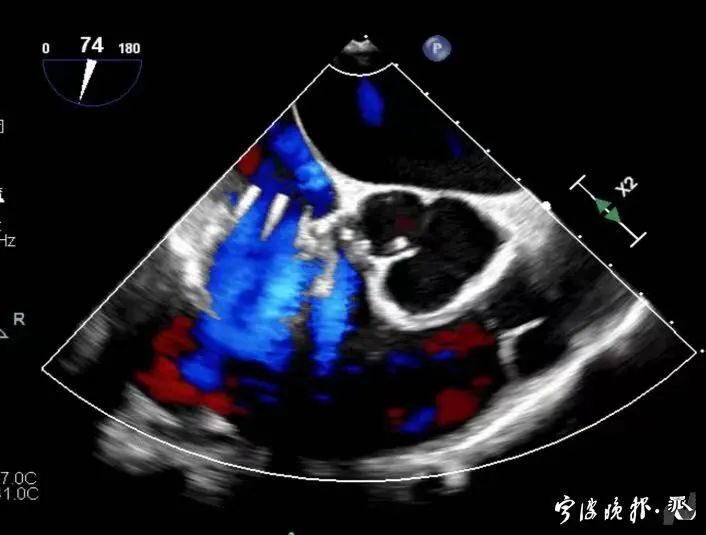

術前食道心超示三尖瓣重度反流

術后食道心超示三尖瓣反流消失